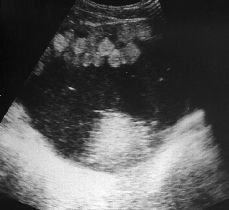

Teratoma quístico de ovario con bolas grasas intraquísticas. A propósito de un caso,

Ovarian cystic teratoma containing balls of fat. A case report,

Aurora Salinas, Manuela Rebolledo, Manuel Escribano, Juan P Alejo, José Moreno